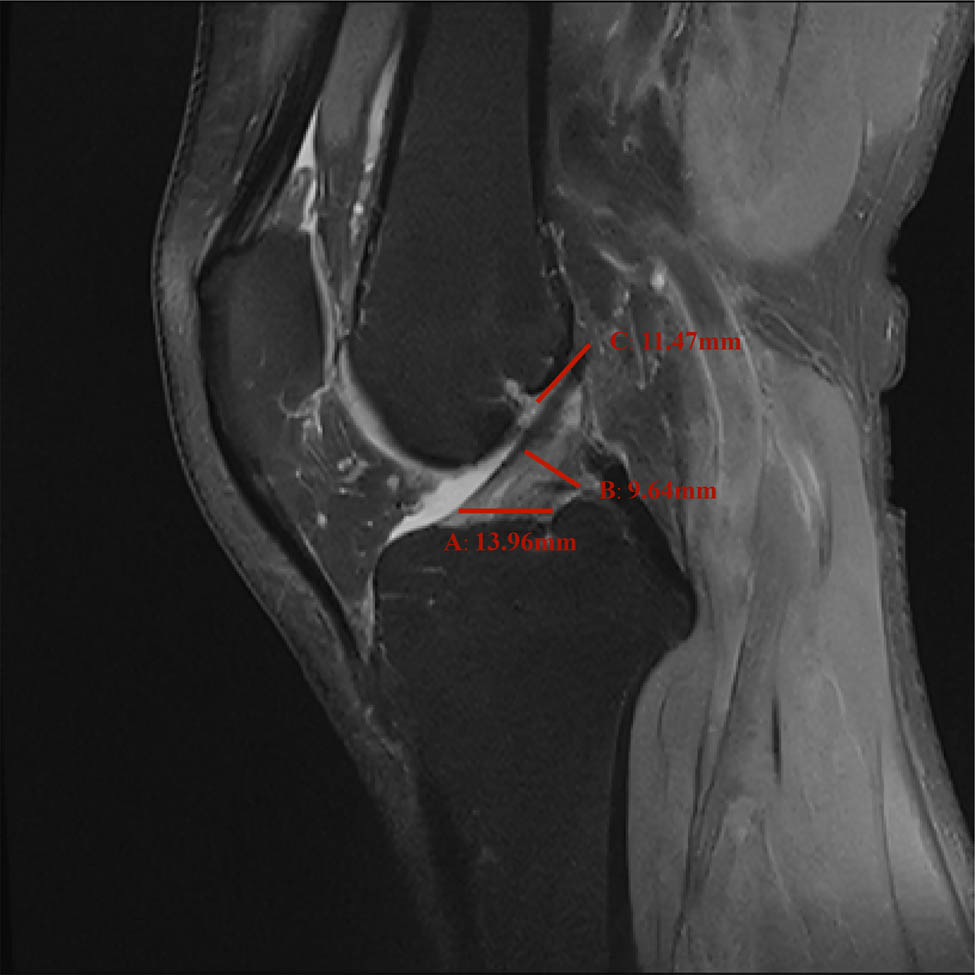

In the sagittal MRI, the ACL originates on the medial surface of the lateral femoral condyle, passes antero-inferiorly, and terminates at the bone surface in front of the tibial intercondylar bulge. The normal ACL in the MRI of the knee joint appears as a relatively loose mid-to-low signal shadow. There is a line-like, stripe-like medium or high shadow separation at its attachment. The origin point of the ACL was selected to be measured obliquely below the posterior part of the lateral femoral condyle of the ligament. The midpoint diameter of the ACL was measured at the midpoint of the ACL perpendicular to the cruciate ligament. The insertion point of the ACL measured was selected to be 2 mm above the bone surface in front of the tibial intercondylar bulge. Figure 1 shows a schematic diagram of the measurement of the diameter of the ACL.

Schematic picture of the diameter measurement of each point of the ACL: A represents insertion point, B represents midpoint, and C represents origin point of the ACL.